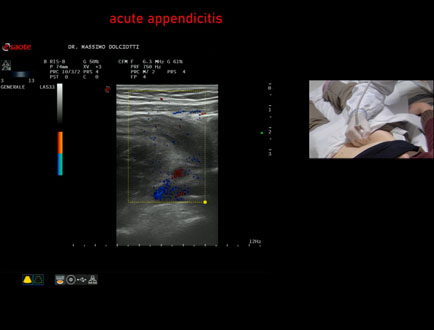

Data inserimento: 15/01/2026

Ecografia del: 07/01/2025

Strumento: Esaote MyLab Eight

Sonda: Lineare Multifrequenza 3-13 MHz

Età Paziente: F 39 anni

Motivazione dell'esame: dolori addominali epiastrici da 2 gg, anche notturni, non nausea, non vomito, non diarrea, non febbre, diuresi normale, nicturia saltuariamente.

Commento all'esame: le immagini ed il video documentano, in sede ileo-cecale, appendice di spessore aumentato (11 mm - V.N. inferiore a 6 mm). Gli elementi ecografici segnalati orientano per appendicite acuta.

Conclusioni: appendicite acuta (acute appendicitis).

In collaborazione: Dr.ssa Marica Manfredi - Ancona, Dr. Ilir Qose - Ancona

Presentazione: Dr. Massimo Dolciotti - Ancona